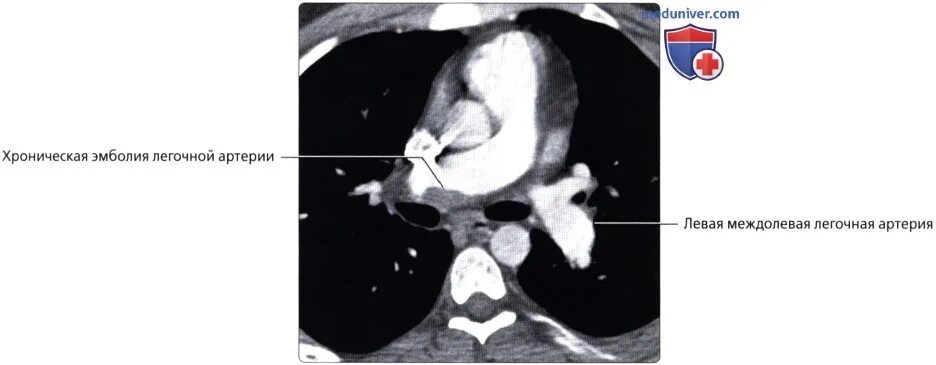

Легочный ствол легкого